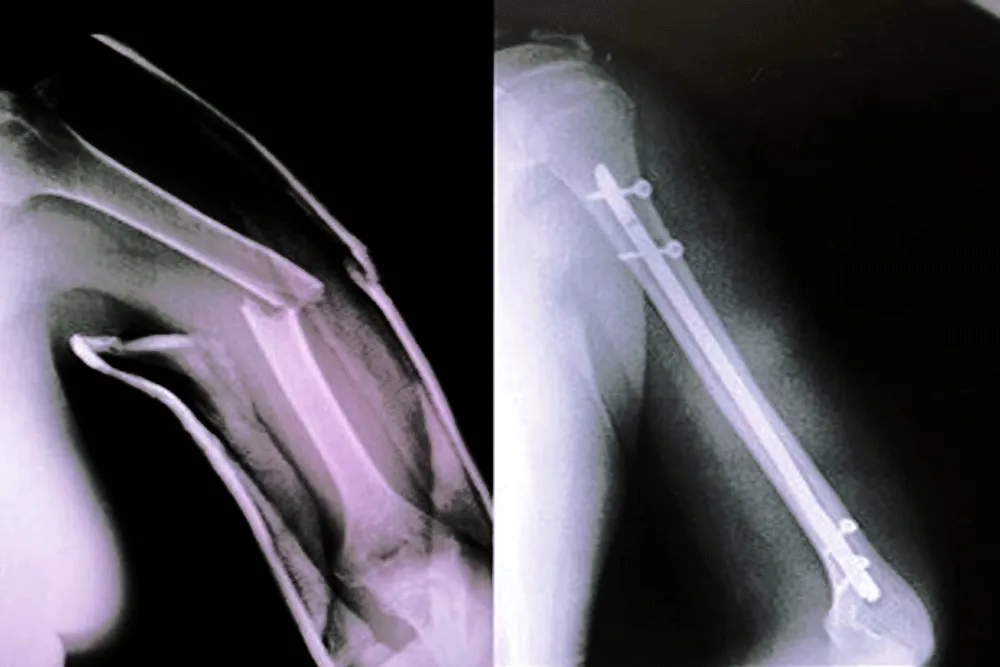

Utilizamos tecnología de vanguardia y técnicas quirúrgicas innovadoras para garantizar los mejores resultados posibles para sus pacientes.

Egresado de la Universidad San Luis Gonzaga de Ica, con estudios de posgrado en la Universidad Federico Villarreal. Con más de 15 años de experiencia, el Dr. Vladimir Inca se ha especializado en el tratamiento de fracturas, lesiones articulares y cirugías de prótesis. Su enfoque se basa en brindar atención personalizada y soluciones efectivas para mejorar tu calidad de vida y recuperar tu movilidad.